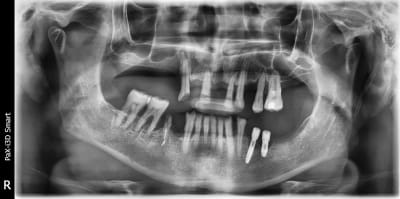

Je sais que certains sont experts en la matière ici alors s'ils peuvent m'aider à identifier le modèle des deux implants en 35 et 36 ça serait super bien que je doute de la longévité de ceux ci

une rétro stp pour être sûr....

mais ils ont une bonne tête de xive....

http://whatimplantisthat.com/implant/xive-s-plus-2/

mais amha, c'est vraiment compromis....

Voilà la rétro

Tu en penses quoi? Cratérisation trop importante?